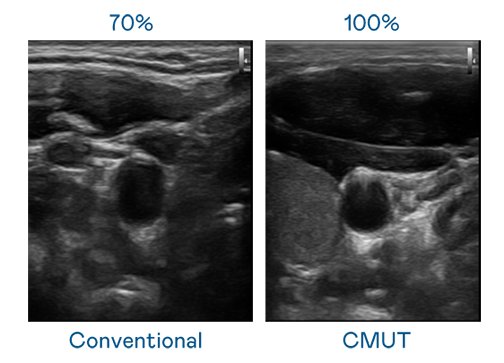

CMUT 技术是一种用电容式微机电元件来产生超音波讯号的技术。与传统 PZT 压电式技术相比,CMUT 频宽增加 30%,更宽频的超音波讯号让影像解析度大幅提升,是实现高影像品质医疗超音波扫描、促进精准医疗发展的关键技术。

超音波影像的解析度高低,首先取决于探头能发出的讯号频宽。果冻传媒原创 CMUT 可提供高清晰的超音波讯号,提供高频宽、高灵敏度、影像纹理细节更高的超音波影像,协助医护人员缩短影像判读时间及利用精准的医疗影像进行诊断。